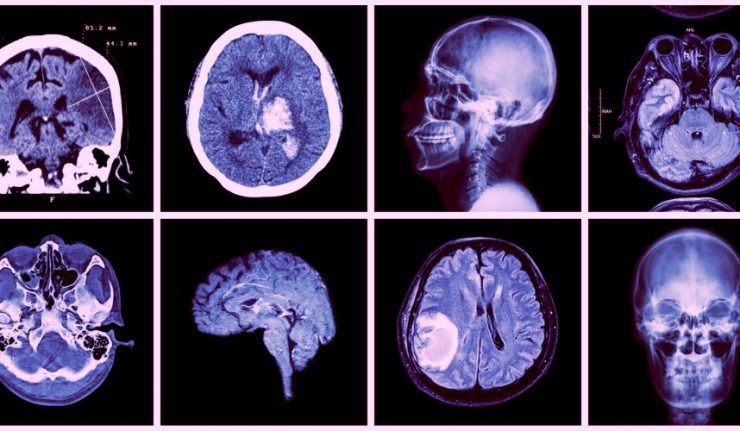

Les accidents vasculaires cérébraux (AVC) constituent une affection grave du système nerveux central. Ils se traduisent par la survenue brutale (très souvent en moins d’une heure) d’un déficit neurologique focal.

C’est donc une urgence médicale absolue à laquelle les services de neurologie et des urgences médico-chirurgicales du CHU de Tlemcen mobilisent tout leur personnel médical et paramédical, ainsi que leur moyen matériel pour l’accueil, la réalisation des mesures d’urgence, le recueil d’informations et la surveillance des patients victimes d’un AVC, comme l’expliquera le chef du service de neurologie, Pr. Bouchenak Khelladi Djaouad. «L’AVC est une anomalie fonctionnelle ou une pathologie du système nerveux central provoquée par une pathologie des artères et des veines, où le pronostic vital est très souvent en jeu.

Et donc tout se joue dès l’apparition de cet accident et surtout l’heure de début des symptômes. Nos médecins procèdent dans le même temps au recueil d’informations auprès de la famille ou de l’entourage pour connaître les circonstances, les antécédents et les traitements en cours. Tous ces renseignements sont consignés dans le dossier de soins. Notre équipe médicale a également pour rôle d’informer, d’écouter et de rassurer la famille du patient pris en charge. Il est nécessaire d’apprécier l’état neurologique du patient en salle de soins, et s’il est conscient ou inconscient. Il s’agit aussi d’évaluer le patient et de détecter la présence de convulsions, d’hémiplégie de la main, du bras ou du membre inférieur, et de troubles associés, avant de procéder aux examens approfondis, d’assurer la surveillance, le suivi des complications et organiser les soins de suite ».